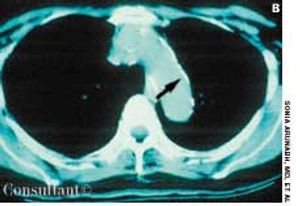

A 64-year-old woman with a history of diabetes, hypertension, and lymphoma was admitted to the hospital with a dull headache, conjunctival congestion, and slight dyspnea. Her pulse rate was 96 beats per minute; blood pressure, 146/68 mm Hg; and respiration rate, 22 breaths per minute. She also had increased jugular venous distention; cardiovascular and chest examination findings were normal. Edema of both arms and dilated blood vessels on the anterior chest wall were noted.